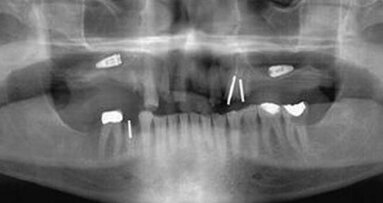

Les radiographies intraorales et panoramiques ne sont pas des images tridimensionnelles (3D) et les cliniciens ne peuvent en obtenir que des mesures ...